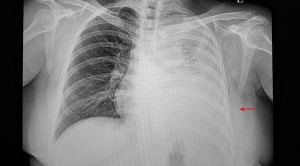

• Rontgen vs USG Toraks untuk Diagnosis Pneumothorax

Rontgen vs USG Toraks untuk Diagnosis Pneumothorax

Pemeriksaan rontgen dan USG toraks merupakan modalitas yang digunakan untuk menegakan diagnosis pneumothorax. Pemilihan antara kedua pemeriksaan tersebut sering kali tidak dipahami...(Baca Selengkapnya)

• Interpretasi Rontgen Toraks

Interpretasi Rontgen Toraks

Cara membaca atau interpretasi rontgen toraks (chest x-rays) memerlukan pengertian anatomi dan fisiologi dari organ dada serta pengertian akan limitasi dari pemeriksaan...(Baca Selengkapnya)